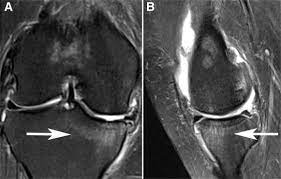

A B Subchondral Bone Marrow Edema Is Seen On Short Tau Inversion Download Scientific Diagram